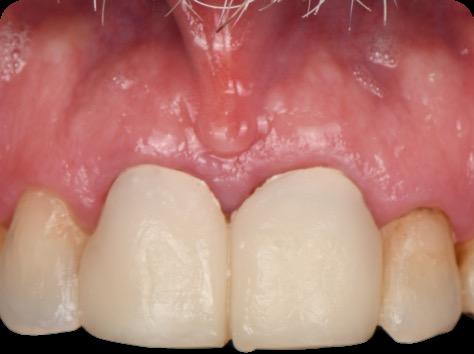

Fig 3. Provisional restorations on central incisors and gingival images. The gingival contours were optimal, and the gingival phenotype was thick.

Fig 5. Central incisors extracted using minimally invasive protocol. Alveolar bone and gingival tissues were intact after extraction